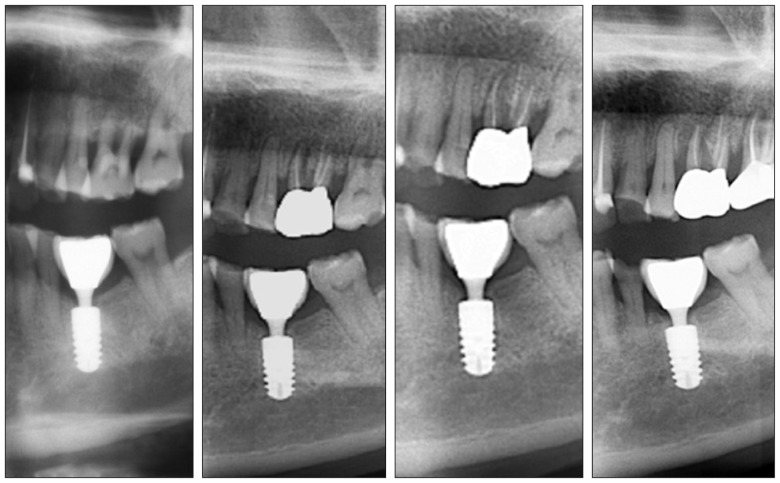

对于应用平台转移减少种植体边缘骨吸收的原因,目前尚无定论,可能的生物学因素有生物学宽度水平转移,使种植体-基台界面向种植体长轴方向移动,减少了此处聚集的细菌对边缘骨的影响[56]。也有学者[57]认为,采用平台转移修复后,在种植体平台建立紧密的软组织封闭,阻挡细菌入侵而导致颈部骨吸收。也有学者应用有限元分析力学因素,平台转移可改变颈部的应力分布,使应力更集中在种植体中心[58],减少了种植体周围骨组织的应力[59]。目前,许多种植体厂商均推出具有平台转移的种植体,如Ankylos、Nobel Active、Astra等。具有平台转移设计的种植体尤其适用于前牙区,种植体颈部骨组织的稳定保证了前牙种植修复后长期的美学效果。北京大学口腔医院种植科自2000年来植入5 000余枚平台转移方式连接的种植体,临床观察报告种植体颈部骨组织及前牙区美学效果稳定[60]–[62](图9)。

图 9. 2004年患者左下第一磨牙平台转移种植体完成修复,2016年种植体颈部无骨吸收,种植体颈部没有出现所谓“生物学宽度”.

Fig 9 A platform switching implant was placed replacing a patient's left mandibular first molar and restored in 2004. There was no marginal bone recession and appearance of so-called “bio logical width” until the last follow-up in 2016

A:2004年复查;B:2009年复查;C:2014年复查;D:2016年复查。